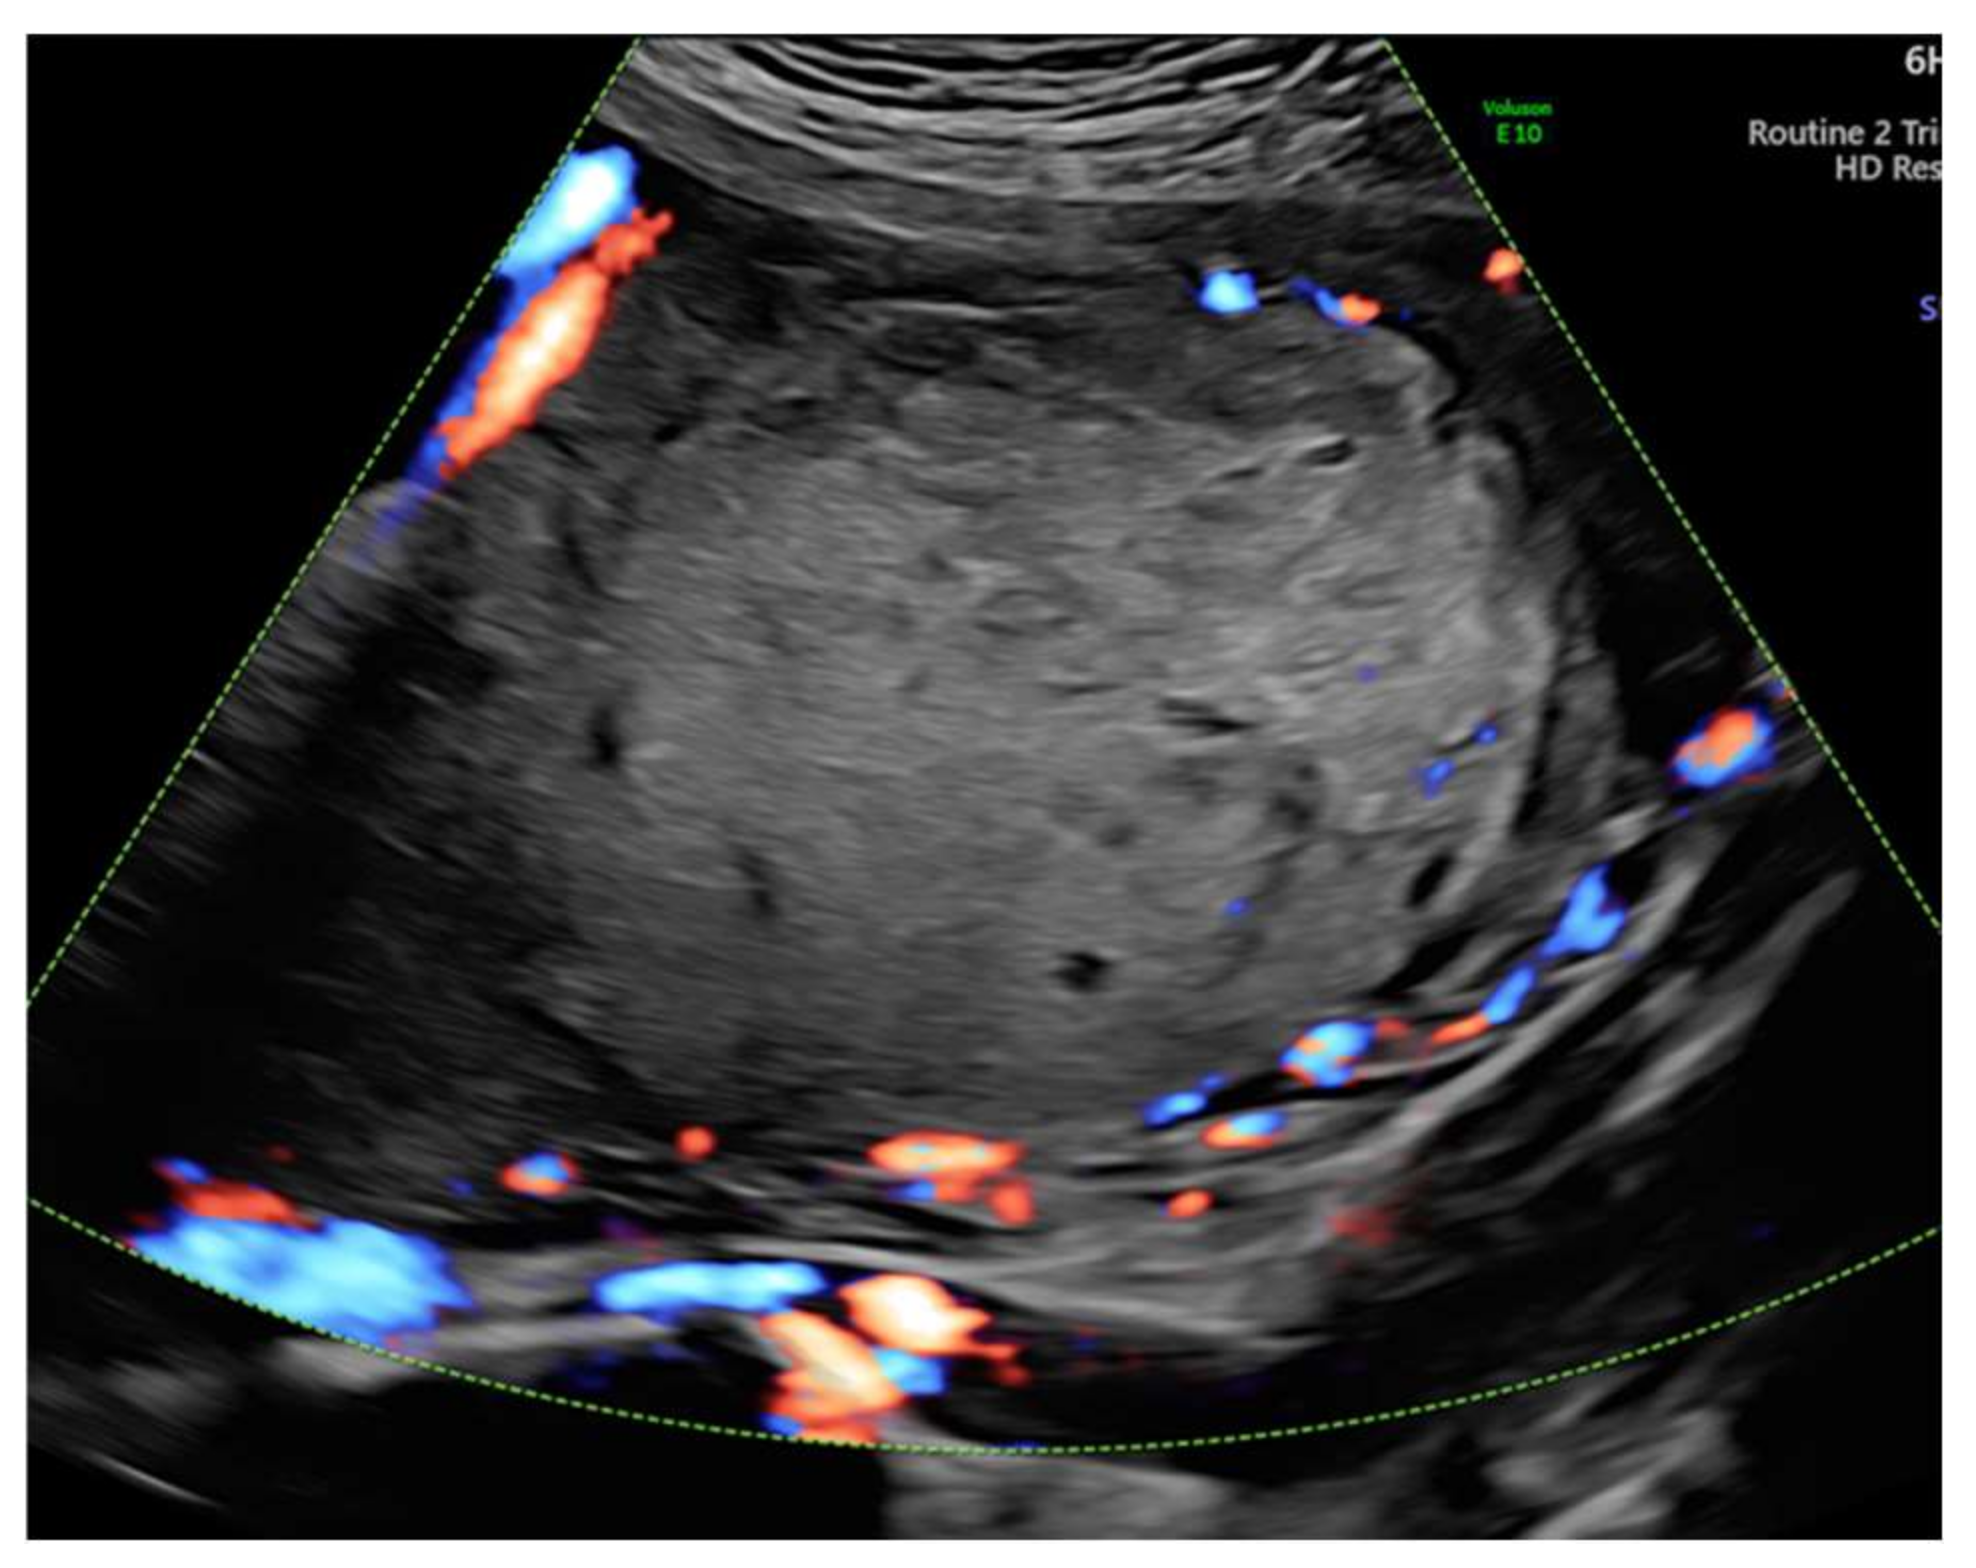

3. Case Report